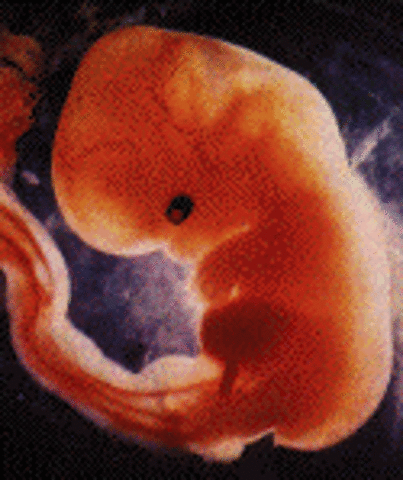

• Week 7: Arms and Legs Begin to Grow

Week 7: Arms and Legs Begin to Grow

Embryo is around 13mm, heart is beating with one chamber, dividing wall is formed in the heart, arm and leg buds begin to grow, lower jaw and vocal cords begin to form, mouth opening is formed, inner ear is being created, digestive tract is developing, navel string being created, lungs, liver, pancreas, and thyroid gland are being formed